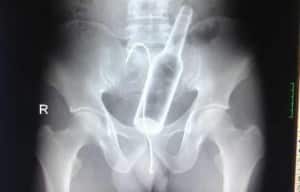

La passion de Zac Mitchell, qui est aussi son métier, a bien failli lui couter la vie. Mais il s’en est sorti avec « seulement » un doigt sectionné. En s’occupant du bétail, dans sa ferme dans l’ouest de l’Australie, Zac s’est fait attaquer par un taureau. Il a perdu son pouce lors de l’accident. Les chirurgiens ont trouvé la solution pour qu’il retrouve la totale mobilité de sa main blessée… Ils lui ont greffé le pouce des doigts de pied, à la main.

Un taureau enragé a foncé sur Zac Mitchell, 20 ans, alors qu’il s’occupait de ses bovins, dans la ferme où il travail. L’animal l’a coincé contre une barrière et la force qu’il a exercée lui a arraché le tendon de la main qui est sorti de son bras. Une bonne partie de la peau de son pouce a été arrachée. La partie du pouce enlevée a même été conservée dans une glacière par son collègue qui a récupéré le morceau après l’accident. Mais les chirurgiens n’ont pas réussi à rattaché le morceau à sa main.

Il a eu quelques jours pour prendre cette décision

Ils ont eu l’idée de lui greffer son doigt de pied à la main. De la sorte, il pourra garder toute sa motricité de la main et retrouver son travail qu’il aimait tant. Zac a tout de même pris quelques jours pour réfléchir et donner son accord. Une fois conscient de ce qui l’attendait, il aura fallu huit heures aux chirurgiens pour réaliser l’opération. Mais Zac a certainement pris la bonne décision, car comme l’explique le docteur Sean Nicklin, qui a procédé à l’opération, cela ne sert à rien d’avoir quatre doigts, si on n’a pas de pouce pour appréhender les objets. Alors que vivre avec un doigt de pied en moins n’est pas handicapant, si on rééduque correctement.